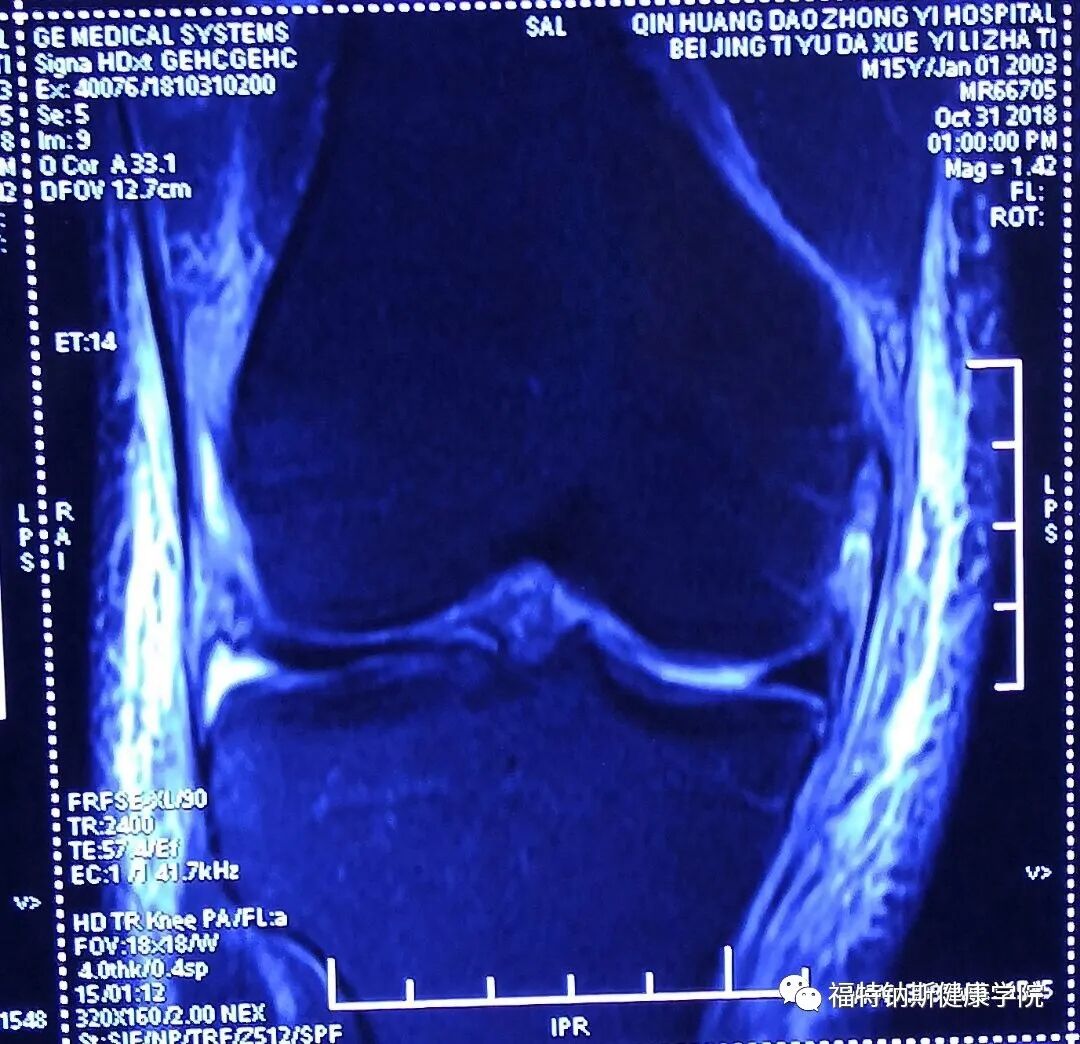

大家好,我是Dean,我是一名在美国执业的物理治疗师和运动损伤防护师。感谢美国南加州大学运动机能与物理治疗学系的邀请,我于2012年随团队一起来到中国开展物理治疗教育。 近年来我一直持续在中国与陈月博士福特钠斯团队合作开展一年两次的上、下肢运动康复的物理治疗继续教育课程。我的治疗和教学课程融合了运动损伤防护背景及物理治疗教育背景和受训经历,将使用手法技术重建活动范围和功能,并同时结合渐进性地运动功能训练。 我希望大家能从接下来的公众号的更文中有所收获。我的目标是以我自己这次严重的膝关节损伤为例,来展示一个在多种组织结构受损的损伤案例中,如何基于组织愈合速率来达到评估损伤,并推进康复的良好流程。这个膝关节受伤的案例中有三种不同的组织结构受损,它们对于治疗的方式及愈合时间的要求均是不同的。 Dean Caswell,PT, OCS, ATC, AT/L, CSCS 一、韧带评估测试(续) Ligament Testing Evaluation Continued LCL/FCL Attachment Sites:Origin lateral femoral epicondyle, joins the biceps femurs tendon before attaching to fibular head. 外侧副韧带/腓侧副韧带起止点:起于股骨外上髁;与股二头肌肌腱结合后止于腓骨小头 二、外侧副韧带损伤评估 0/0 继续观看 【大咖专栏】Dean博士教你如何系统评估膝关节运动损伤 LCL Palpation 外侧副韧带触诊 0/0 继续观看 【大咖专栏】Dean博士教你如何系统评估膝关节运动损伤 LCL Testing 外侧副韧带测试 1、外侧副韧带损伤常见于以下情况: Direct blow to the inside of the knee, such as during a football tackle 膝关节内侧直接受到横向的力,如足球当中飞铲 Quickly changing directions or pivoting on one foot, such as in soccer or basketball 在足球或篮球运动中快速变向或是脚部的扭转 Landing awkwardly from a jump, such as during volleyball or basketball 在排球或足球运动中,跳起后错误的落地 People may also note instability in their knee, particularly with side-to-side or pivoting activities. 人们通常感觉他们的膝关节不稳,尤其是横向不稳或是扭转活动时不稳 Isolated LCL tears are less common than other ligament injuries, such as medial collateral ligament (MCL) or anterior cruciate ligament (ACL) tears. They are most often seen in athletes and alongside other injuries, such as knee dislocations 单独的外侧副韧带撕裂相较于其他韧带(如内侧副韧带,前交叉韧带)并不常见。在运动员群体里常见这样的损伤,并且是伴随其他损伤出现的,比如膝关节脱臼。 2、LCL损伤分级 Grade1 Grade 1 lateral ligament sprain symptoms include tenderness on the outside of the knee over the ligament. Usually, there will be little or no swelling. When the knee is bent to 30 degrees and force applied to the inside of the knee which puts the ligament under stress, pain is felt but there is no joint laxity. This is known as the varus stress test. 一级的外侧副韧带拉伤症状包括膝关节外侧韧带上方疼痛;通常可见少许肿胀或无肿胀;膝关节屈曲30度后,由内侧向外施加一个横向的力使外侧副韧带受力,可激惹痛感,但没有松弛感,这个测试被称作内翻试验。 Grade2 With a grade 2 LCL sprain, you will have significant tenderness on the outside of your knee, over the lateral ligament. You will likely have some swelling. A varus stress test will indicate pain and some laxity in your joint, although there is a definite endpoint indicating the ligament is still intact. 二级外侧副韧带拉伤症状包括明显的膝关节外侧疼痛,韧带上方疼痛;可见肿胀;内翻应力测试可见激惹痛与关节松弛感,但同时可见关节终末感由此可推断韧带还是连着的,没有完全断裂。 Grade3 A grade 3 lateral ligament sprain is a complete tear of the ligament. Pain can vary and may be actually less than a grade 2 sprain. When stressing the knee there is significant joint laxity and you may have a very unstable knee. 三级外侧副韧带拉伤是韧带安全撕裂,其痛感可以且很可能弱与二级拉伤;内翻应力测试可见明显关节松弛感开合感,关节极其不稳定。 3、Dean膝关节外侧副韧带试验结果 Findings of LCL TEST: Dean’s Knee 1、Palpation 触诊: Tenderness at origin/insertion sites, minimal to no pain at center 韧带起止点均有明显痛感;韧带中部轻度痛感或无痛感 Pain Scale to palpation with light touch 3/10 轻触痛感评分3/10 2、Ligament test 韧带试验: Significant movement at joint with laxity at ligament 明显的关节开合感,及韧带松弛感 No Significant pain with test 试验未见痛感 三、Cinical Reasoning (Previous Blog) 临床推断: (前文) Q&A Q1 Based on MRI below what would you grade MCL Tear? 基于下面的核磁结果请为患者内侧副韧带损伤分级: A1 Grade 3 Tear 三级撕裂: highlighted area of MCL with continuous highlight across length of tendon area. 内侧副韧带可见高亮信号;肌腱走向上连续的高亮信号 Q2 What is the current rehabilitation concept regarding repair for MCL tears? 现在针对内侧副韧带的损伤康复有哪些方面需要考虑? A2 The consensus is that isolated MCL tears rarely require operative repair, while treatment of severe combined ruptures of the MCL and anterior cruciate ligament or PCL would require reconstruction. [1] A study found that nonoperative and operative treatments of medial collateral ligament injuries lead to equally good results. Another indication for surgical intervention would be persistent instability, with surgery consisting of tissue repair and imbrication. Often, reinforcement with an allograft is necessary. 共识认为单独的内侧副韧带撕裂一般很少需要手术修复,然而严重的内侧副韧带结合前交叉韧带或后交叉韧带撕裂的治疗需要手术重建。 [1]有研究表明对于内侧副韧带的治疗手术与非手术对比均可见较好的疗效。另一个手术的指征是连续性不稳,手术包括组织重建和覆盖。通常来说,用自体移植物进行加固是很有必要的。 Grade 1 and 2 sprains are routinely treated non-operatively. They may be braced with a knee sleeve or a double-upright hinged knee orthosis, individualized to the patient's discomfort. Crutches are only necessary for a few days. These injuries represent incomplete tears and allow for a rapid return to activities. 一级二级的拉伤通常会选择保守治疗;患者可以个性化需求佩戴如套袖型双铰链类型的支具。也可能需要患者拄拐几天。这类的损伤意味着韧带的不完全撕裂,及较为快速的活动恢复 Historically, grade 3 tears were treated operatively but currently are routinely treated nonoperatively. In the past, nonoperative treatment meant a long leg cast. Currently, bracing with a hinged knee orthosis is common. Some authors recommend immediate braced increase in range of motion (ROM), while others prefer waiting up to 6 weeks with the knee at 30° of flexion. Crutches are usually necessary for 1-2 weeks. 早期的三级拉伤通常采用手术治疗,但现今保守治疗也是常见的选择。在过去,非手术干预意味着长时间的石膏固定,但现今通过铰链式的膝关节支具比较常见。一些作者认为受伤后即刻佩戴支具可以提高关节活动度,另一些人认为6周后待患侧可以屈曲30度后佩戴支具更佳。拐杖通常在早期的1-2周内是必须的 People with grade 1 and 2 injuries usually return to play within 2-3 weeks. People with grade 3 injuries frequently require 6 or more weeks before a return to play. 一级二级患者通常可在2-3周后恢复体育运动,三级患者通常需要6周以上的时间返回体育运动 [1] Dale KM, Bailey JR, Moorman CT 3rd. Surgical Management and Treatment of the Anterior Cruciate Ligament/Medial Collateral Ligament Injured Knee. Clin Sports Med. 2017 Jan. 36 (1):87-103. Q3 What other structures do you see potential injury to in the below MRI Images? 除内侧副韧带外还有哪些组织可能受到了损伤 A3 Highlights at medial and lateral hamstring tendons 内侧和外侧腘绳肌肌腱可见高亮信号 Highlights at medial & lateral meniscus 内侧和外侧半月板可见高亮信号 MRI影像: 持续更新中,敬请期待!